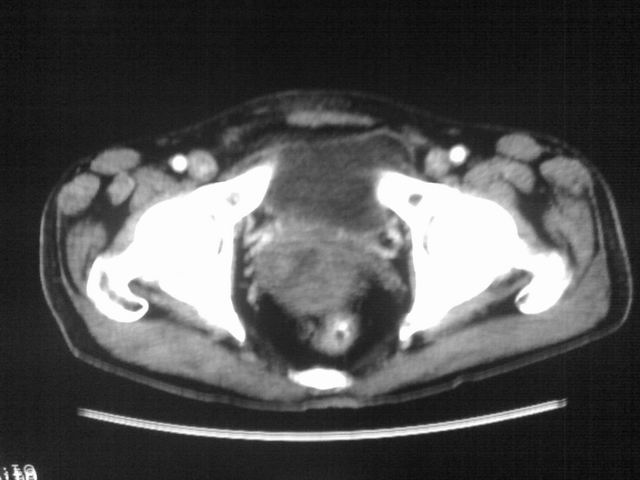

患者m 56岁,盆腔及下腹部胀痛半年,加重1月余,消瘦\中重度贫血.(附:平扫时直肠的高信号为,残留的钡剂).补一下病史:胃镜及纤维结肠镜均无明显异常.

膀胱后方及直肠前方见巨大混杂密度影,与前列腺相连且向膀胱内突入,精囊腺显示不清;考虑前列腺癌侵犯精囊、膀胱。

膀胱及直肠间有不规侧的软组织密度影,内密度不均匀。其内有坏死囊变,前列腺及精囊腺,膀胱后壁受浸。结合病史考虑腹膜后肉瘤可能性大。